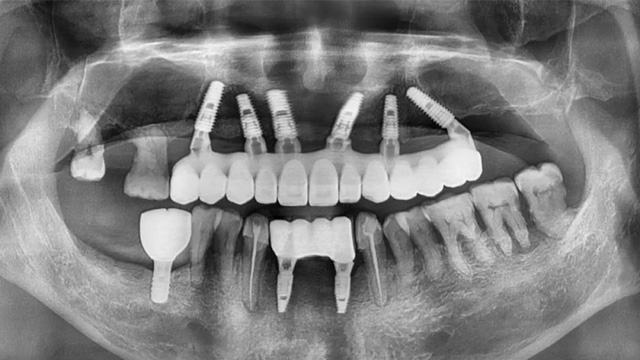

安女士的口腔情况比较复杂,剩余的几颗上牙都是松动牙,下面也仅有几颗门牙还能保留,综合考量后,李阳军医生为她制订了上半口即拔即种,下半口拔1颗松动牙、2颗智齿后即刻种植两颗的治疗方案。这样,只需要种植8颗就能恢复全口咀嚼功能。

安女士半口种植全景片(种植前)

李阳军医生坦言,安女士的上半口手术具有一定难度。由于骨密度较差,骨量也不够,6颗种植体中有4颗需要特殊术式种植,其中两颗为倾斜种植,她的前牙位置还做了大量的植骨。

李阳军医生对半口全口无牙颌种植具有丰富经验,整个手术不到一个半小时就完成了,由于手术时已是下午五点多,戴牙时间推迟到了第二天。

术前,安女士提到比较担心术中的疼痛问题,李阳军医生为她制订了舒适化种植方案。种植手术全程采用静脉滴注镇静,种植位置局部麻醉,整个手术过程非常顺利和高效,顾客感受也非常轻松舒适。

安女士半口种植全景片(种植后)